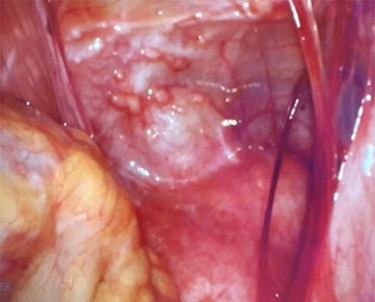

Right ovary with papillary excrescences and grossly abnormal appendix.

On entering the abdomen, the terminal ileum and cecum were grossly normal, while the right ovary showed papillary excrescences on the serosal surface (Fig. 3). The appendix was proximally distended with distal serosal injection and chronic scarring into the pelvis (Fig. 3). An appendectomy was performed (Fig. 5A). Scattered peritoneal nodules were visualized on the abdominal wall anterior to the uterus (Fig. 4), and several biopsies were taken. Cut sections of the appendix revealed uniformly firm, white tissue throughout the entire specimen with a possible centrally located, pinpoint lumen, suggesting fibrous obliteration. No well-circumscribed lesion was identified; however, histopathology showed the appendiceal wall was diffusely expanded by an irregular, wavy spindle cell proliferation involving the mucosa, submucosa, muscularis propria and subserosal tissue (Fig. 5B and C). Immunohistochemical stains highlighted a mixture of S100/SOX10-positive cells and CD34-positive cells, consistent with appendiceal neurofibroma (Fig. 5D). Pathologic diagnosis of the peritoneal biopsies was low-grade serous neoplasia.